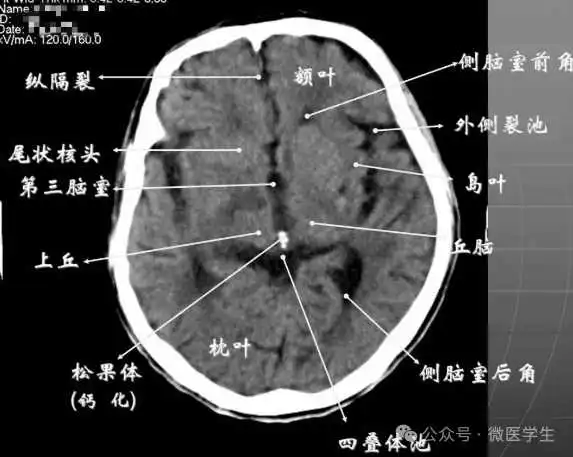

- 基底核、丘脑。

- 内囊前脚(前肢);尾状核和豆状核之间。

- 内囊膝部和后脚(后肢):位于豆状核(由外侧的壳核和内侧的苍白球组成)及丘脑之间。

- 壳核的外侧:外囊、屏状核、最外囊、岛叶(脑岛)。

- 四叠体池:两侧枕叶之间,池内有松果体,向前与第三脑室连接。